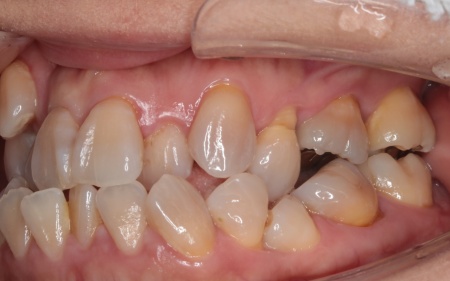

治療前

はじめの相談内容 「見た目が気になる。また、食べ物が噛みにくい」とご相談いただきました。

診断結果 拝見したところ、上下の歯がデコボコに乱れて生えていました。

歯の大きさに対して顎が小さいため、歯が正常に並びきらず、全体的な噛み合わせのバランスも崩れています。

噛み合わせを詳しく検査したところ、実際にしっかりと噛み合っているのは一部の歯だけで、このまま放置すると特定の歯に負担が集中し、将来的に痛みや違和感が生じるおそれがあります。

また、銀歯が装着されている右下奥歯は以前神経を抜く治療がされていましたが、現在は歯の具合が良好とはいえず、温存が難しい状態です。